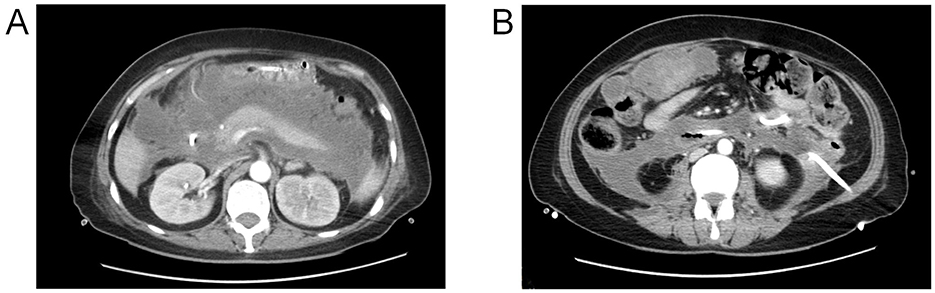

Video-assisted retroperitoneal debridement confirmed a perforation in the anterior wall of the descending duodenum via methylene blue leakage test (Figure 2A). We removed most necrotic tissue and placed a 32Fr drainage catheter adjacent to the fistula. Post-operative drainage was effective, with the fistula orifice location confirmed by assessing the spatial relationship between the drainage catheter tip and the duodenum on post-operative CT images (Figure 2B). However, severe malnutrition necessitated urgent enteral access. Nutritional intervention: Due to severe malnutrition and risks of conventional methods (blind insertion risks tube misplacement into necrotic cavities; ultrasound limitations in duodenal imaging; endoscopic air insufflation risks fistula expansion), In alignment with the patient's and family's preference for a non-surgical approach, bedside electromagnetic navigation guided nasojejunal tube placement was performed. Utilizing real-time electromagnetic tracking and 3D spatial mapping, the catheter tip was successfully positioned within the proximal jejunum (Figures 2C, D). Post-procedural water-soluble iodinated contrast radiography confirmed proper positioning of the catheter tip distal to the ligament of Treitz (Figure 2E).

Figure 2. (A) Intraoperative visualization of the duodenal fistula orifice (white arrow); (B) Post-operative CT demonstrated the position of the drainage tube tip (white arrow) and the location of the duodenal fistula (red arrow); (C, D) use of electromagnetic navigation for inserting the nasojejunal tube; (E) the jejunal feeding tube tip position (white arrow) and duodenal fistula orifice localization (red arrow) was achieved via water-soluble iodinated contrast radiography.